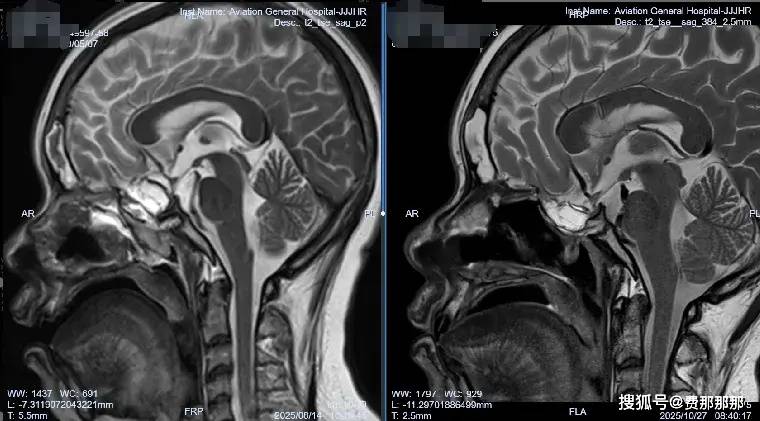

肖庆主任决定采取分阶段治疗策略:首先在2025年8月13日进行“腰大池置管引流”,建立初步引流通道;随后在8月21日实施“脑室腹壁外引流术”,建立持续引流通道。“精准的脑脊液管理是真菌性颅内感染治疗的关键。”肖主任强调,“我们不仅要控制感染,更要通过精细的引流调节,维持正常的颅内环境,为大脑恢复创造最佳条件。”

当引流管夹闭一周后,李女士没有出现任何不适,医疗团队知道,他们的治疗策略奏效了。2025年10月28日,肖庆主任为李女士成功结扎了引流管。那一刻,病房里洋溢着久违的轻松气氛。

肖庆主任表示,这个病例的成功得益于“个体化的脑脊液管理策略”与“精准的抗真菌治疗”的完美结合。“真菌性颅内感染治疗的最大挑战在于,它容易导致脑室系统粘连,进而形成脑积水。而通过精准的脑脊液外引流管理,我们不仅控制了颅内压力,还直接改善了药物分布,防止了并发症的发生。”

如今,李女士已重返正常生活。医生叮嘱她一个月后复查脑脊液、三个月后复查头颅影像学检查。“我知道康复之路还很长,但至少现在我看到了希望。”出院时,李女士说道。